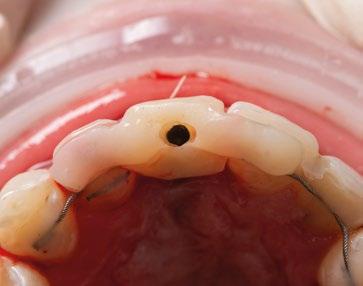

En el caso de obtener suficiente torque, podríamos incluso valorar la opción de cargar dicho implante. En este caso lo que hacemos es planificar también un pilar con el fin de trabajar nuestra prótesis a nivel gingival, siguiendo la filosofía de “One Abutment-One Time (OAOT)”.

12.- Colocamos aditamento N1TM Base XealTM con el fin de trabajar la prótesis a nivel gingivall. (Figura 28)

13.- Colocamos pilar provisional.